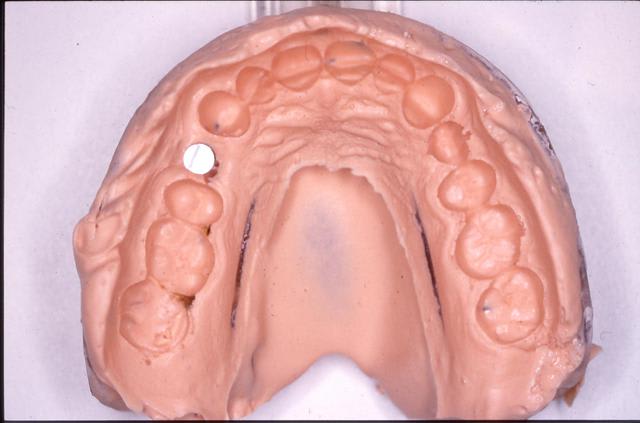

prise empreinte